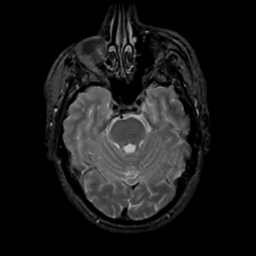

MR Study #10, April 28, 1991 -- Slice #15